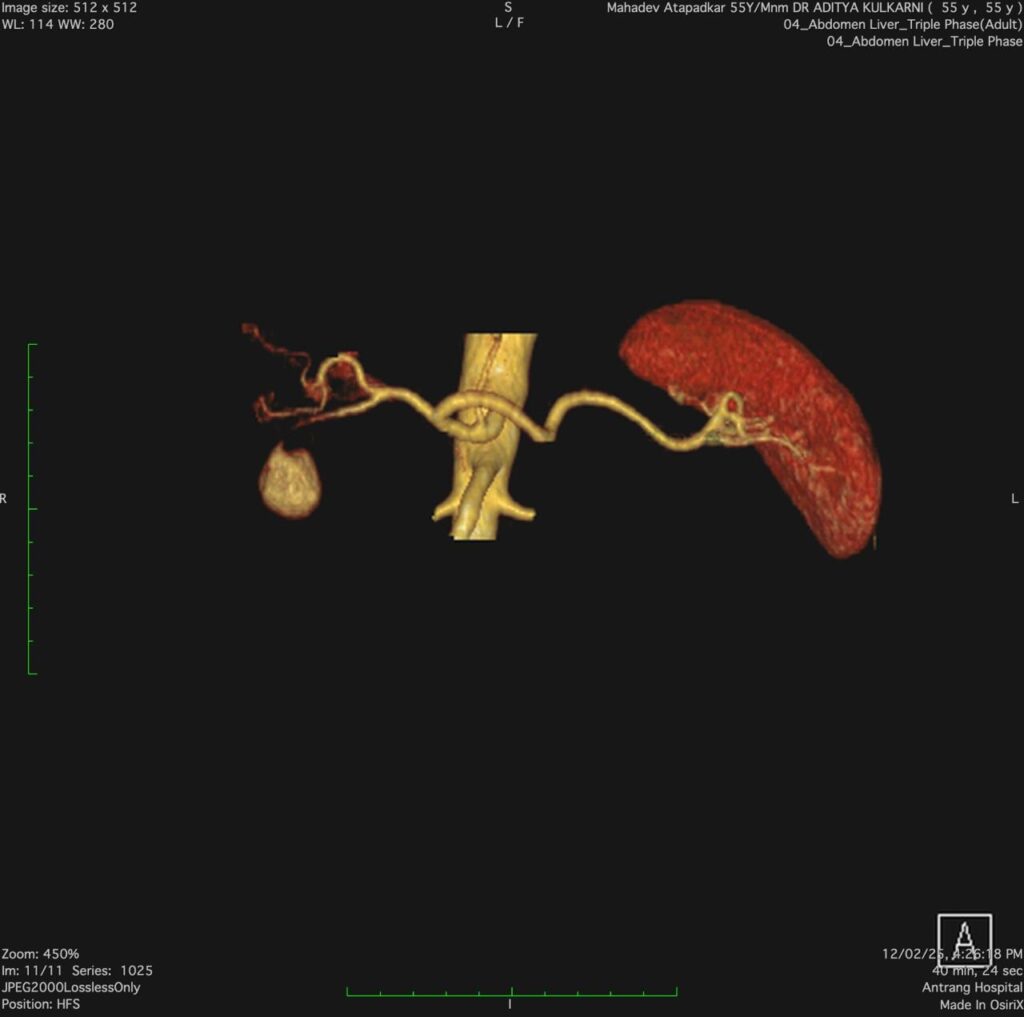

A 53 years- old male presented with a history of repeated GI bleeding for 20days. He had undergone UGI scopy and colonoscopy twice elsewhere with no obvious source of bleed. He was referred to us for further management Initial investigations revealed low haemoglobin levels (3.4), necessitating multiple blood transfusions. CECT abdomen done revealed 4.2×3.4cm pseudo aneurysm arising from Gastro duodenal artery branch within pseudocyst. There was bleeding within pseudocyst. Endoscopic ultrasound (EUS) guided coil +glue was performed to manage the pseudo aneurysm. Post procedure imaging showed Complete Occlusion of the pseudo aneurysm, and the patient was stabilized with supportive care, including IV fluids, antibiotics, and proton pump inhibitors (PPI)

Pseudo aneurysms in chronic pancreatitis are rare but can be fatal due to spontaneous rupture. The primary arteries involved are the splenic, gastroduodenal arteries. The diagnostic approach includes contrast- enhanced computed tomography (CECT), magnetic resonance angiography (MAR), and catheter angiography. Management options include endovascular interventions such as coil embolization or glue injection, surgical resection, or a combination of both as per the local expertise.